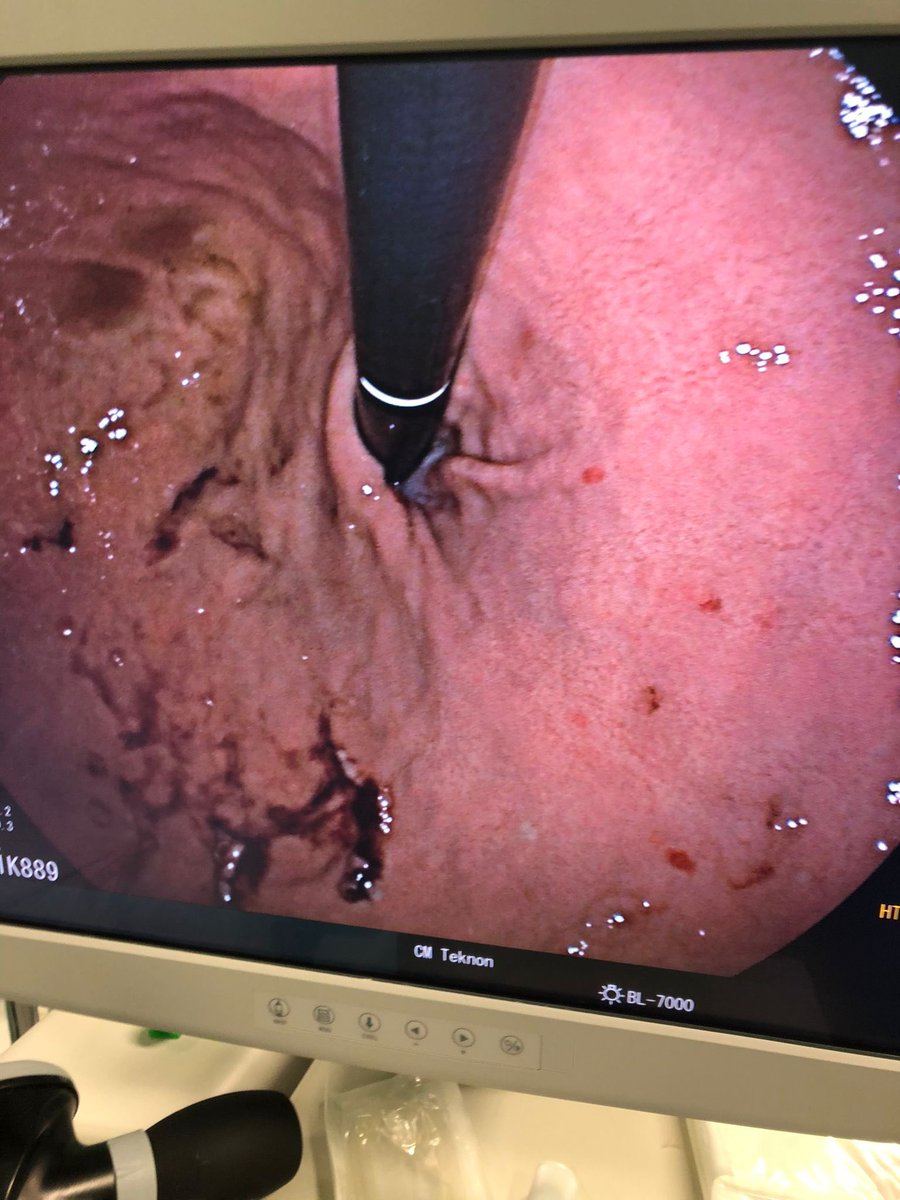

#MedCase 🧓 65 años con ingesta accidental de cuerpo extraño hace 24 horas. Intento fallido de extracción es referida para tratamiento. Endoscopia asistida por cap. Retiro con campaña “artesanal” de Hood. Se observa laceración esofágica y colocación de clips.